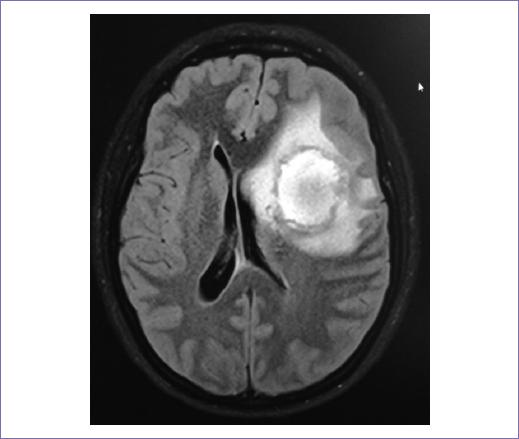

Presentamos el caso de una paciente de 29 años de edad, sin antecedentes familiares de cáncer de mama, exposición a radiación, trauma o alguna enfermedad genética. Inició su padecimiento con una tumoración en la mama izquierda de crecimiento progresivo durante 6 años. Se le realizó biopsia escisional, la cual reportó tumor phyllodes (no se especificó el grado); con este resultado se sometió a escisión amplia de la lesión, sin embargo, presentó recurrencia local ocho meses después, por lo que se refirió a nuestra Institución para valoración y manejo. A la exploración física se encontró en mama izquierda una tumoración de bordes irregulares, multilobulada, de 30 x 20 cm, que infiltraba casi toda la totalidad de la mama, sin adenopatías (Fig. 1). Se le realizó mastectomía simple izquierda con reconstrucción, el reporte histopatológico fue positivo a sarcoma del estroma mamario de alto grado con borde más cercano a 4 mm del lecho quirúrgico.

Figura 1 Resonancia magnética, corte axial, secuencia T1. Se muestra tumoración en mama izquierda, multilobulada, que ocupa su totalidad.